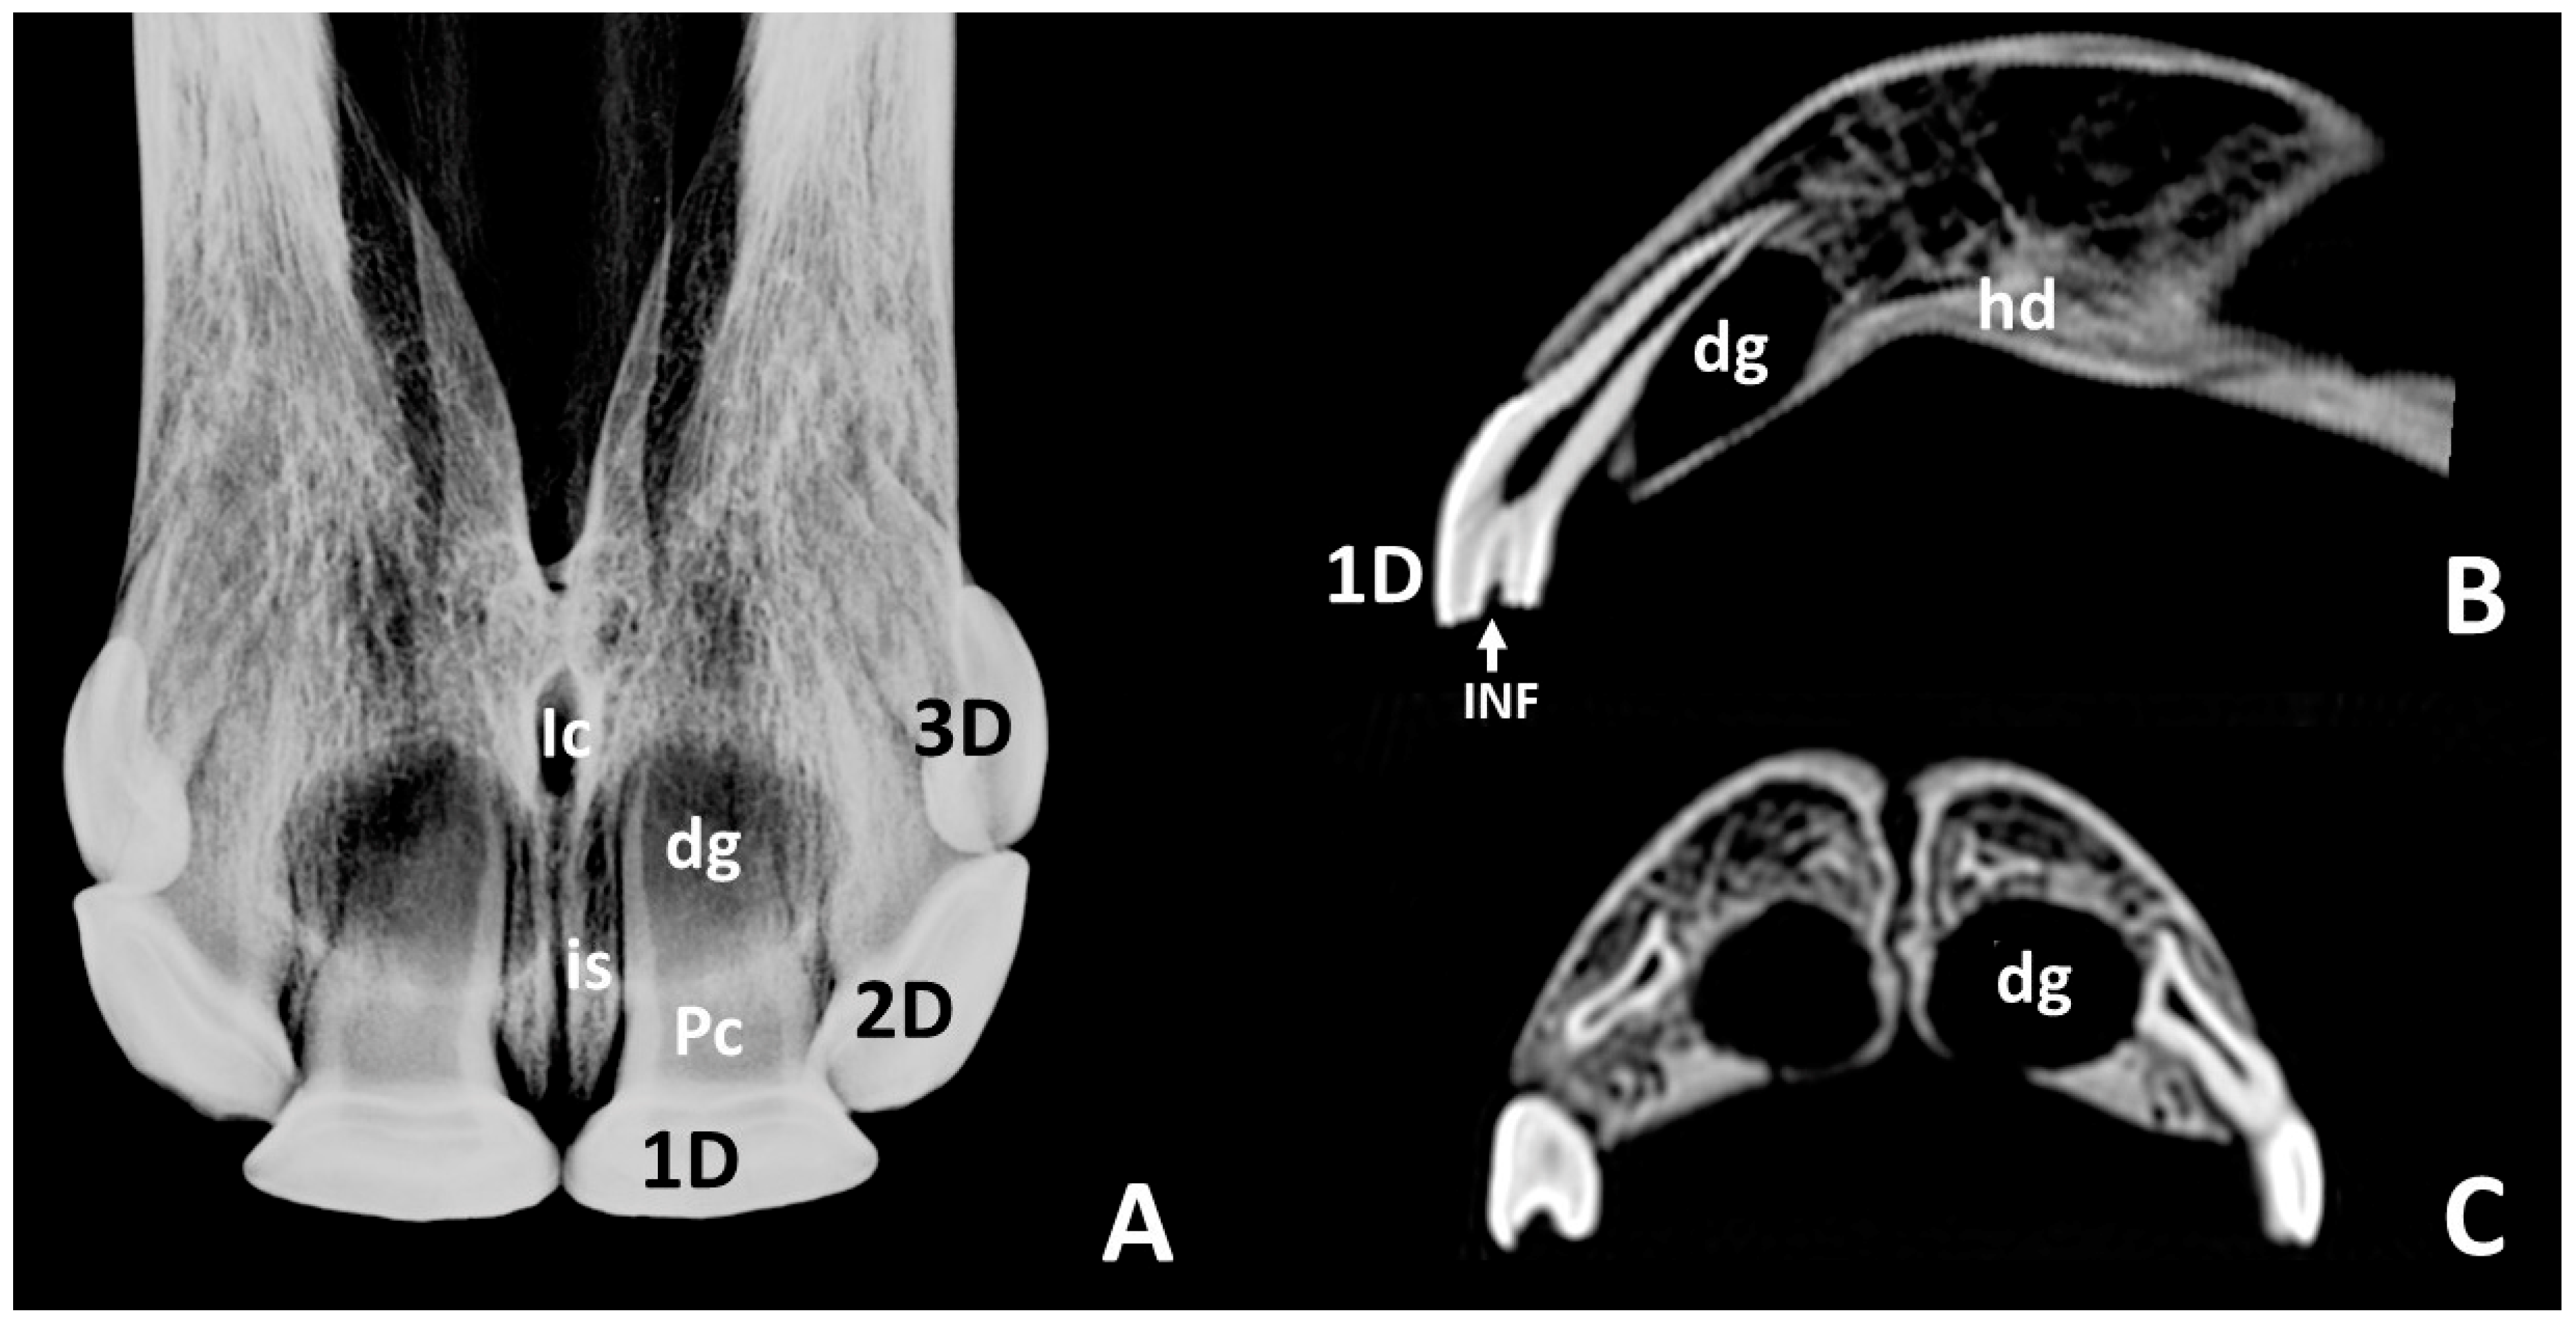

3.2. Radiographic and CT Studies

4.1. Deciduous Incisors: Radiographic and CT Studies

4.2. Permanent Incisors and Alveoli: Radiographic and CT Studies

| 1 1a | Dental germs, round radiolucent areas in the incisive bone No other notorious characteristics | 5 |

| 1b | Dental germs, round radiolucent areas in the incisive bone Circumscribed radiopaque images inside | 4 |

| 1c | Dental germs, unerupted crowns within the incisive bone, hardly any observable radiopacity | 8 |

| 1d | Dental germs, larger unerupted crowns within the incisive bone, greater radiopacity | 4 |

| 2 | Erupted, quite large, and radiopaque | 4 |